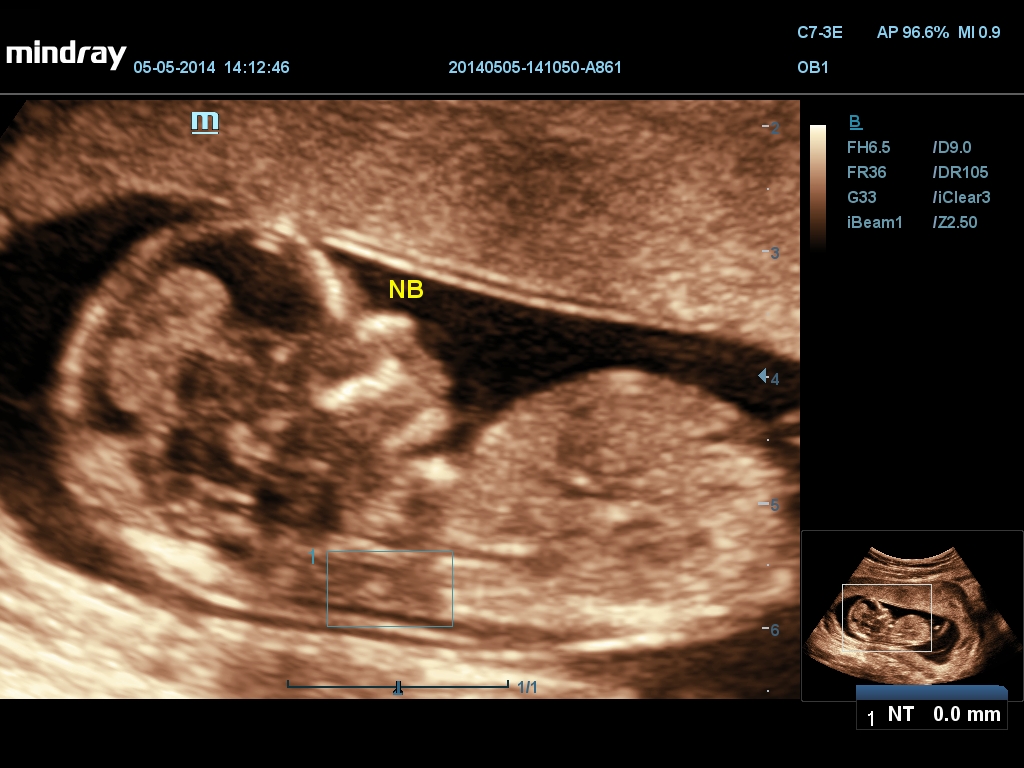

Mindray DC-70 Exp с технологией X-Insight – это узи-аппарат для высококачественной диагностики. Преимущества: высокая эффективность, точность визуализации, результат в «одно касание» с экспертными датчиками. Рекомендуется для государственных учреждений.